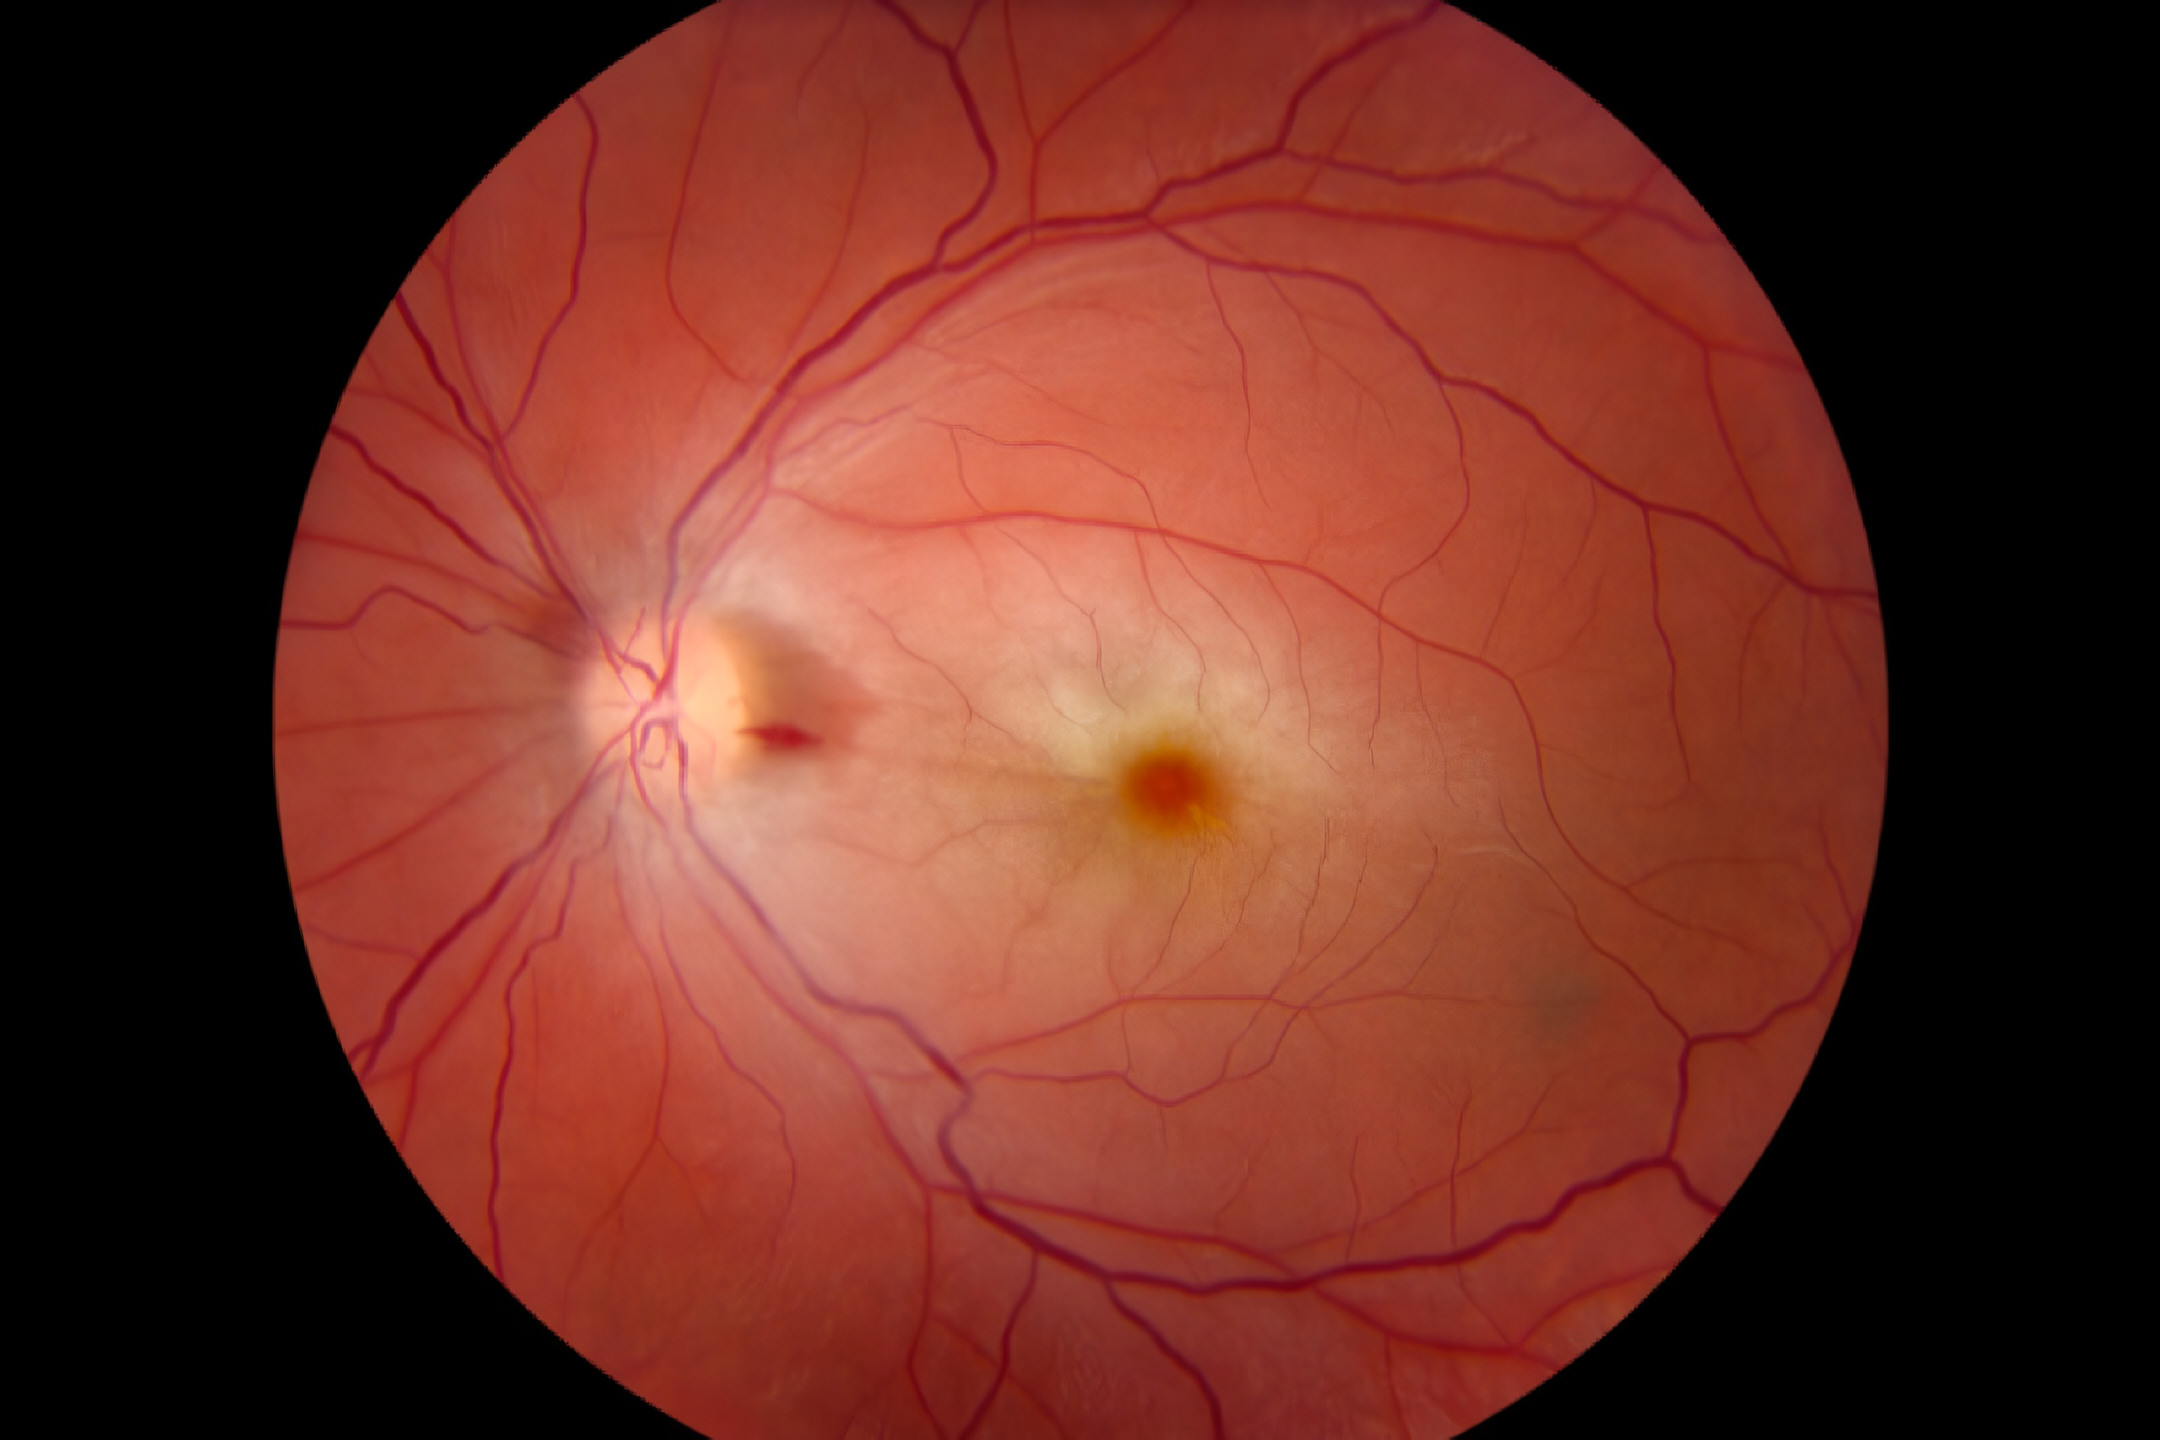

年龄相关性黄斑变性 (AMD)

年龄相关性黄斑变性 (AMD) 是一种主要影响50岁以上的中老年人的常见眼部疾病,会导致显著的中心视力丧失。其风险因素多方面,包括年龄、种族、眼部特征、高血压、高脂血症和动脉硬化等全身性疾病、吸烟和营养不良等生活方式因素以及遗传倾向。AMD分为两种主要类型:干性 (非渗出性或萎缩性) 和湿性 (渗出性)。干性AMD的特征是玻璃膜疣的逐渐积累、色素变化和视网膜萎缩,进展缓慢,导致视力逐渐下降,通常在黄斑区呈现“金箔”外观和视网膜色素上皮的地图状萎缩。相反,湿性AMD涉及视网膜下异常血管的快速生长,导致反复渗出、出血、纤维血管瘢痕形成、色素紊乱和新生血管形成,从而导致迅速而严重的视力丧失。西医对AMD的干预通常侧重于抑制这些异常血管的生长,使用玻璃体腔内注射抗VEGF药物、光动力疗法 (PDT) 或手术等方法。

中医将本病视为“视瞻昏渺”,且认为AMD是脏腑功能随年龄下降、肝肾亏虚、脾气虚弱、气滞血瘀及痰湿积聚的结果。干性AMD主要以虚证为特征,与气血不足和肝肾亏虚有关,而湿性AMD通常以本虚标实为特征,本虚涉及肝肾阴虚、阴虚火旺和气血不足,标实涉及血瘀内阻和痰湿阻络。因此,中医的调理方法根据AMD的具体类型和根本原因而有所不同。一般来说,建议在强光环境下佩戴遮阳帽和太阳镜,在冰雪或水域佩戴滤光镜,以保护眼睛免受光损伤。